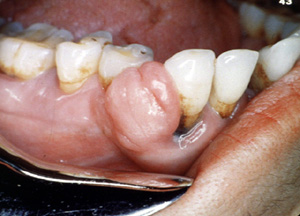

Esta gran lesión se extendió bien en lingual y cambió de sitio algunos de los dientes. Los granulomas periféricos lograrán un tamaño considerable sin tratamiento. La terapia es la biopsia por escisión . Puede ser necesario extender la cirugía  al hueso subyacente para eliminar la lesión. También se indica la eliminación de estímulos irritantes.

Este fibroma  periférico se proyecta desde la encía y se muestra enrojecido. Parece un granuloma.